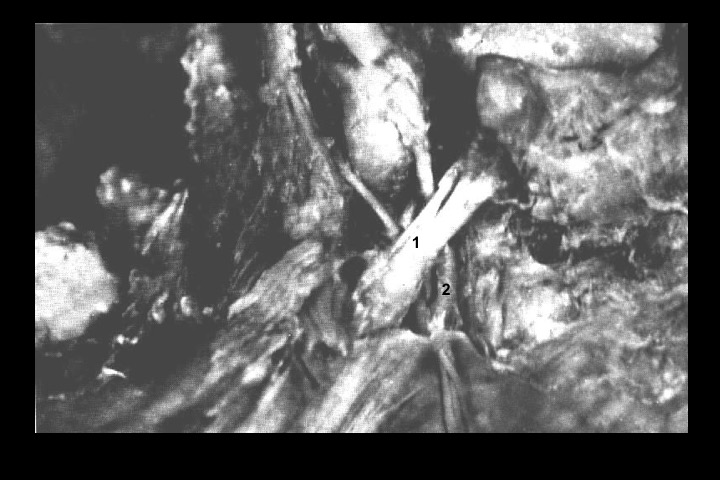

O Prof. Emérito da UFRJ Dr. Adalmir Morterá Dantas está disponibilizando através de nosso website e de nosso canal youtube (cursobom) o Museu de Neuroanatomia, no intuito de promover esta área de conhecimento junto aos estudantes de Medicina.

As figuras são apresentadas em 4 vídeos no youtube e podem ser obtidas via download clicando-se na figura em questão.